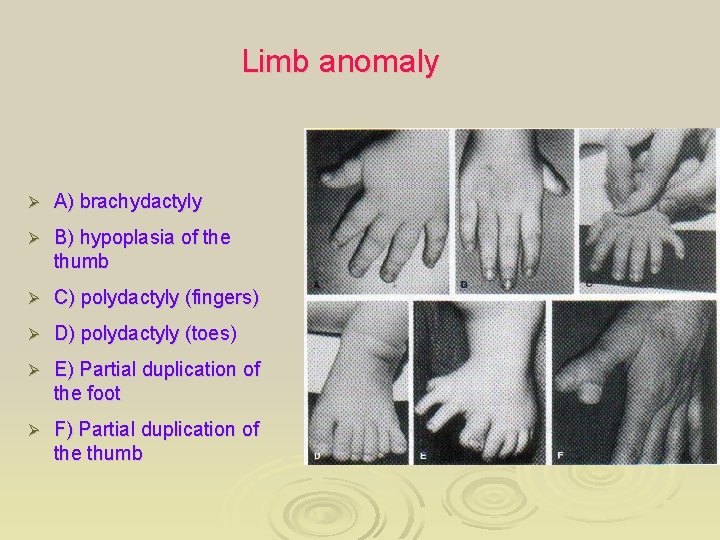

Limb anomaly Ø A) brachydactyly Ø B) hypoplasia of the thumb Ø C) polydactyly (fingers) Ø D) polydactyly (toes) Ø E) Partial duplication of the foot Ø F) Partial duplication of the thumb